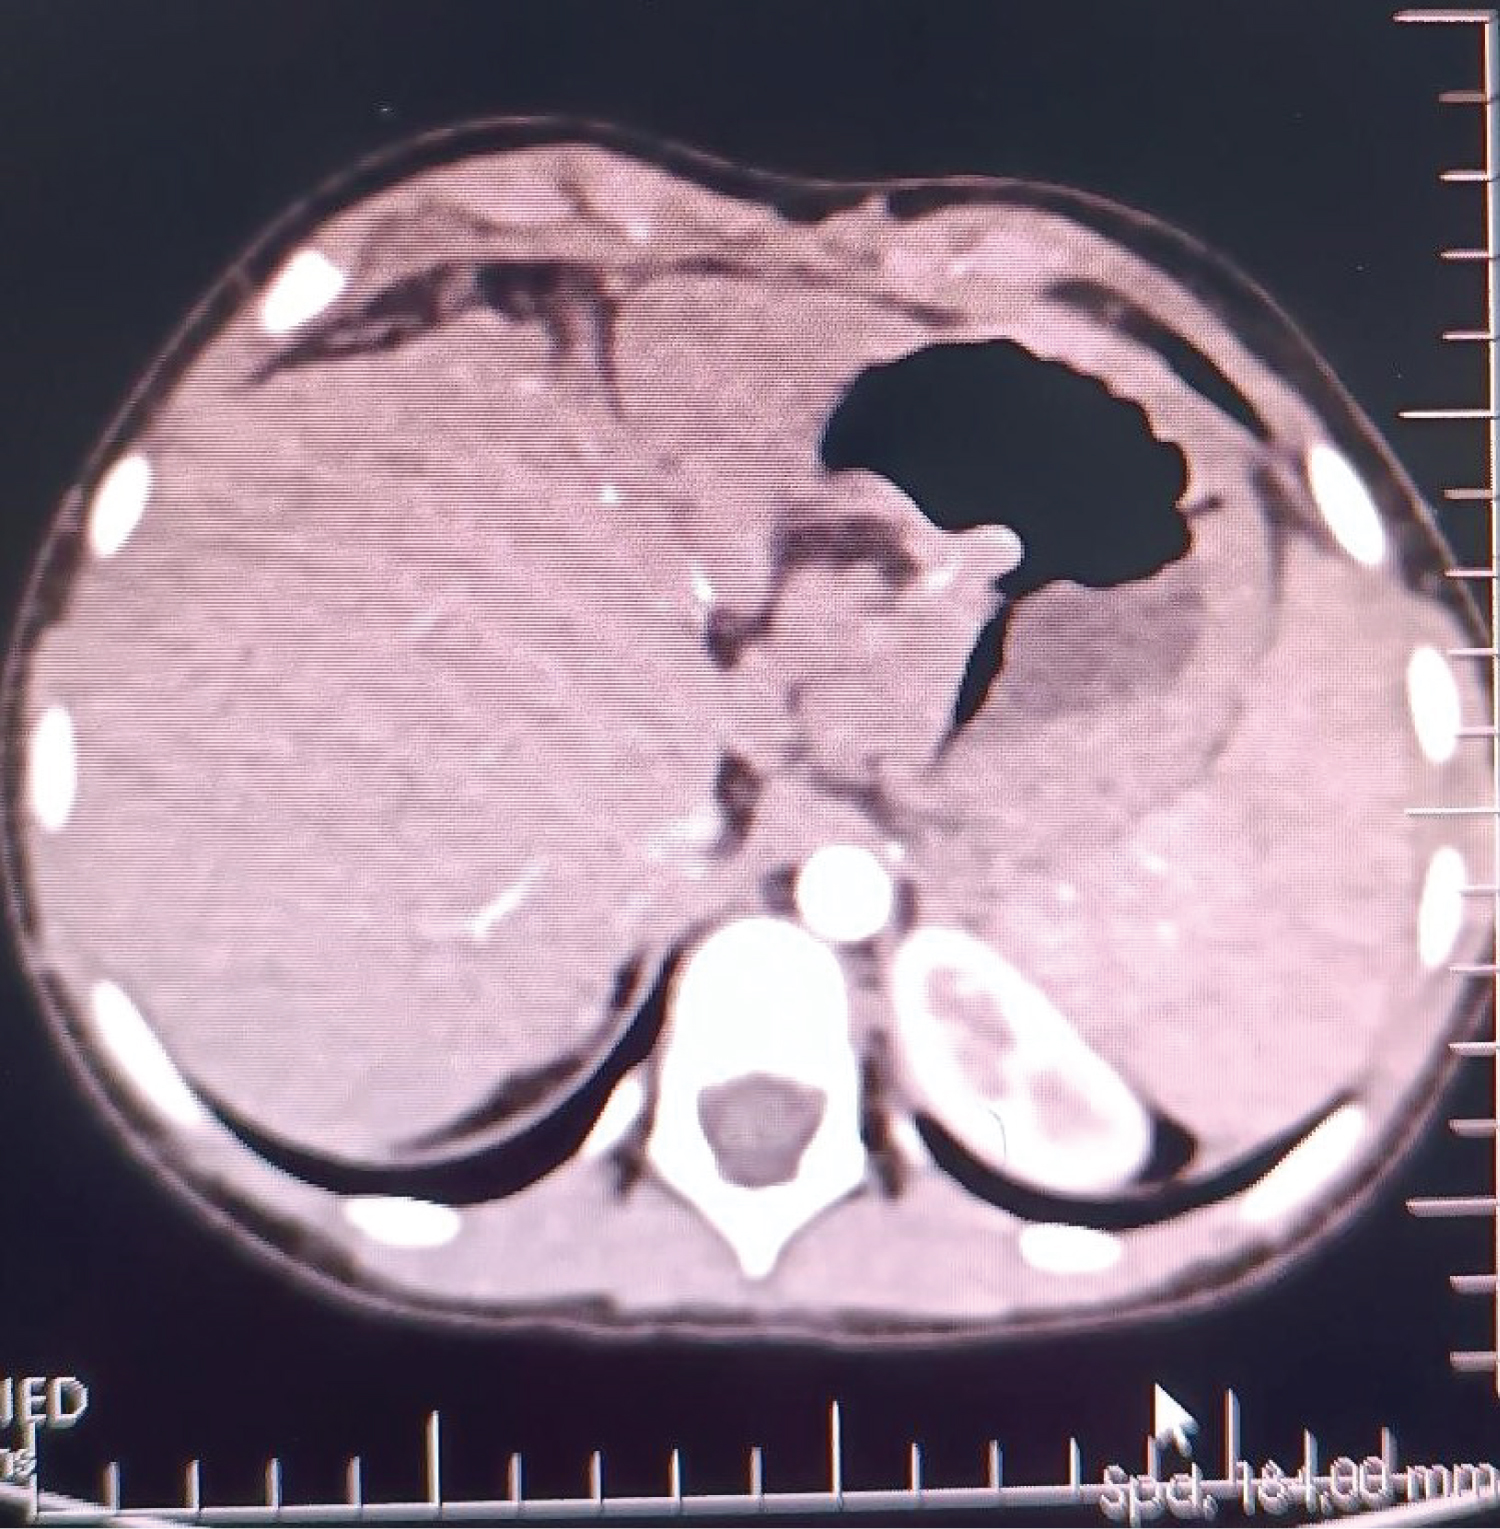

A 6-year-old female (height: 115 cm, weight: 22 kg) patient with pediatric living donor LT for biliary atresia (cirrhosis with portal hypertension) with a pulmonary AVF, HPS, was admitted to an intensive care unit (ICU) transplantation. She had a Kasai operation on the 45 th day after birth to treat biliary atresia. After the Kasai procedure, the patient developed malnutrition due to portal hypertension, hepatosplenomegaly, jaundice, ascites, and esophageal varices. After month 5, dyspnea, platypnea, orthodeoxia, weakness, cyanosis when crying, clubbing, and cyanotic fingertips began to appear. These findings' presence in ESLD patients made us think of HPS, and CE-TTE was then performed, and microbubbles were observed in the left atrium on CE-TTE. A lung perfusion scan revealed an intrapulmonary right-to-left shunt fraction of 25%, and pulmonary arteriography was also diffuse IPVD and pulmonary AVF without capillary phase was detected. In the patient's liver computed tomography (CT)-angiography, diffuse hepatoportal shunt and splenomegaly were found in the liver parenchyma due to the operated biliary atresia (Figure 1). She later developed cirrhosis and was followed up with a diagnosis of cirrhosis until the age of 6 years.

Figure 1: In the patient's liver computed tomography (CT) - angiography, diffuse hepatoportal shunt and splenomegaly were found in the liver parenchyma due to the operated biliary atresia.